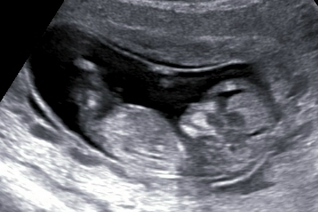

Пол малышаДевчонки, хочу поболтать. Делала узи на 11,5. Врач про пол малыша ничего не сказал. Я мне хоть предположений хочеться. Кстати муж сказал, что личико явного парня. Представляю фотку.

Вот и мне кажется, что по лицу мальчик. А у меня по лицу явная девочка, вроде бы так и вчера по узи сказали, что девочка у нас!